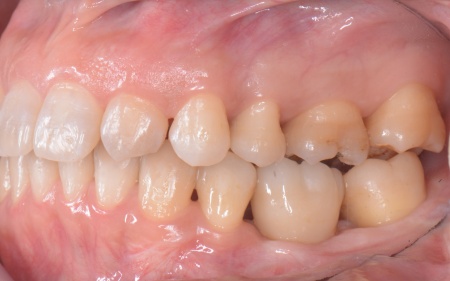

50代女性 インプラント・矯正・被せ物治療で見た目と噛み合わせを改善した症例

「以前治療した左下奥歯が思うように噛めない。また、矯正治療を受けた前歯でうまく噛めない」とご相談いただきました。

拝見したところ、左下奥歯(第1大臼歯)は以前、歯根分割処置が行われていました。

さらに患者様は全体的に歯並びや噛み合わせに問題があり、特に上下の前歯は噛んだ際に隙間ができ食べ物を噛み切りにくい状態です。

また、右の上下奥歯2本に装着されている白い被せ物や銀歯が劣化により歯に合わなくなり、虫歯の再発リスクが高まっていました。